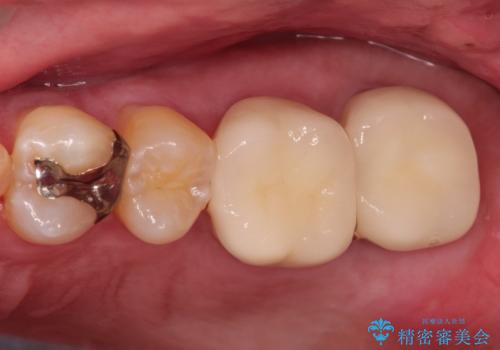

目立つ金歯を自然な色のオールセラミックへ

- 矯正の治療後に目立つ金歯を白くしたいとのことで治療することとなりました。

左上の奥歯に大きな金歯と、その後ろの歯が矯正治療用の仮歯が装着されていました。

これらの歯にオールセラミッククラウンを装着することとなりました。

総合治療が可能な当院ならば、矯正後のセラミックの装着がスムーズに行うことが可能です。